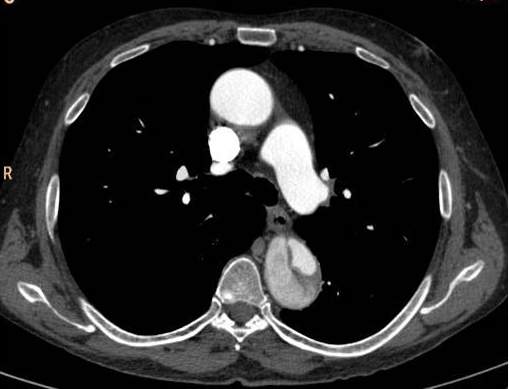

There are two main types of aorta dissection according to the Stanford classification: type “A” when the ascending aorta is involved, and type “B” when the dissection occurs distal to the origin of the left subclavian artery and it does not propagate to the level of ascending aorta or the aortic arch. The two types are distinguished because of their acute complications: type “A” dissection can cause the obstruction of the coronary trunks or, in case of a pericardial rupture, it can cause consequent pericardial tamponade and sudden death. Hence these cases require immediate surgical intervention with a cardiac surgical background. In contrary type “B” dissection can cause the acute obstruction of the abdominal aortic branches and can lead to life threatening conditions only in a subacute manner (intestinal ischemia, renal insufficiency). These conditions can also require surgical intervention (vascular surgery) but they rarely need immediate surgery. Both dissection types have the late stage complication of the development of aneurysm that occurs due to the weakened and constantly expanding vessel wall, which constitutes a growing risk for aortic rupture.

Primary diagnostic imaging is usually performed as an emergency examination, patients are often unstable, or gravely ill and in poor condition. Therefore, CTA is a most advantageous method; it can provide a diagnostic quality imaging even on a non-cooperative patient with. It is crucial to determine the type of dissection (A or B-), the involvement of the supraaortic and abdominal branches, the origin of the side branches, and the anatomy of the false and the real lumen and their permeability. A highly pulsating aortic root can cause diagnostic problems because of the vessel movement. The artifact caused by the moving arterial wall can mimic an intimal-flap, especially at the root of the ascending aorta. However, this can be avoided with ECG gated examination; hence patients with symptoms of acute coronary syndrome should be directed to a centum where ECG gated imaging is available.

Image

The lumen is divided by the detached intimal layer that can be followed from the origin of the left subclavian artery to the descending aorta.

The real lumen shows a fast filling and a more intense contrast enhancement,

while the false lumen shows a less intense contrast enhancement due to its decreased flow.

Fig. 26., 27., 28.: Type B aortic dissection CT angiography

On axial slices, an intima flap can be seen in the ascending aorta

The dissection spreads also into the lumen of supraaortic arteries

Fig. 29., 30.: Type A aortic dissection, ECG-gated CTA examination